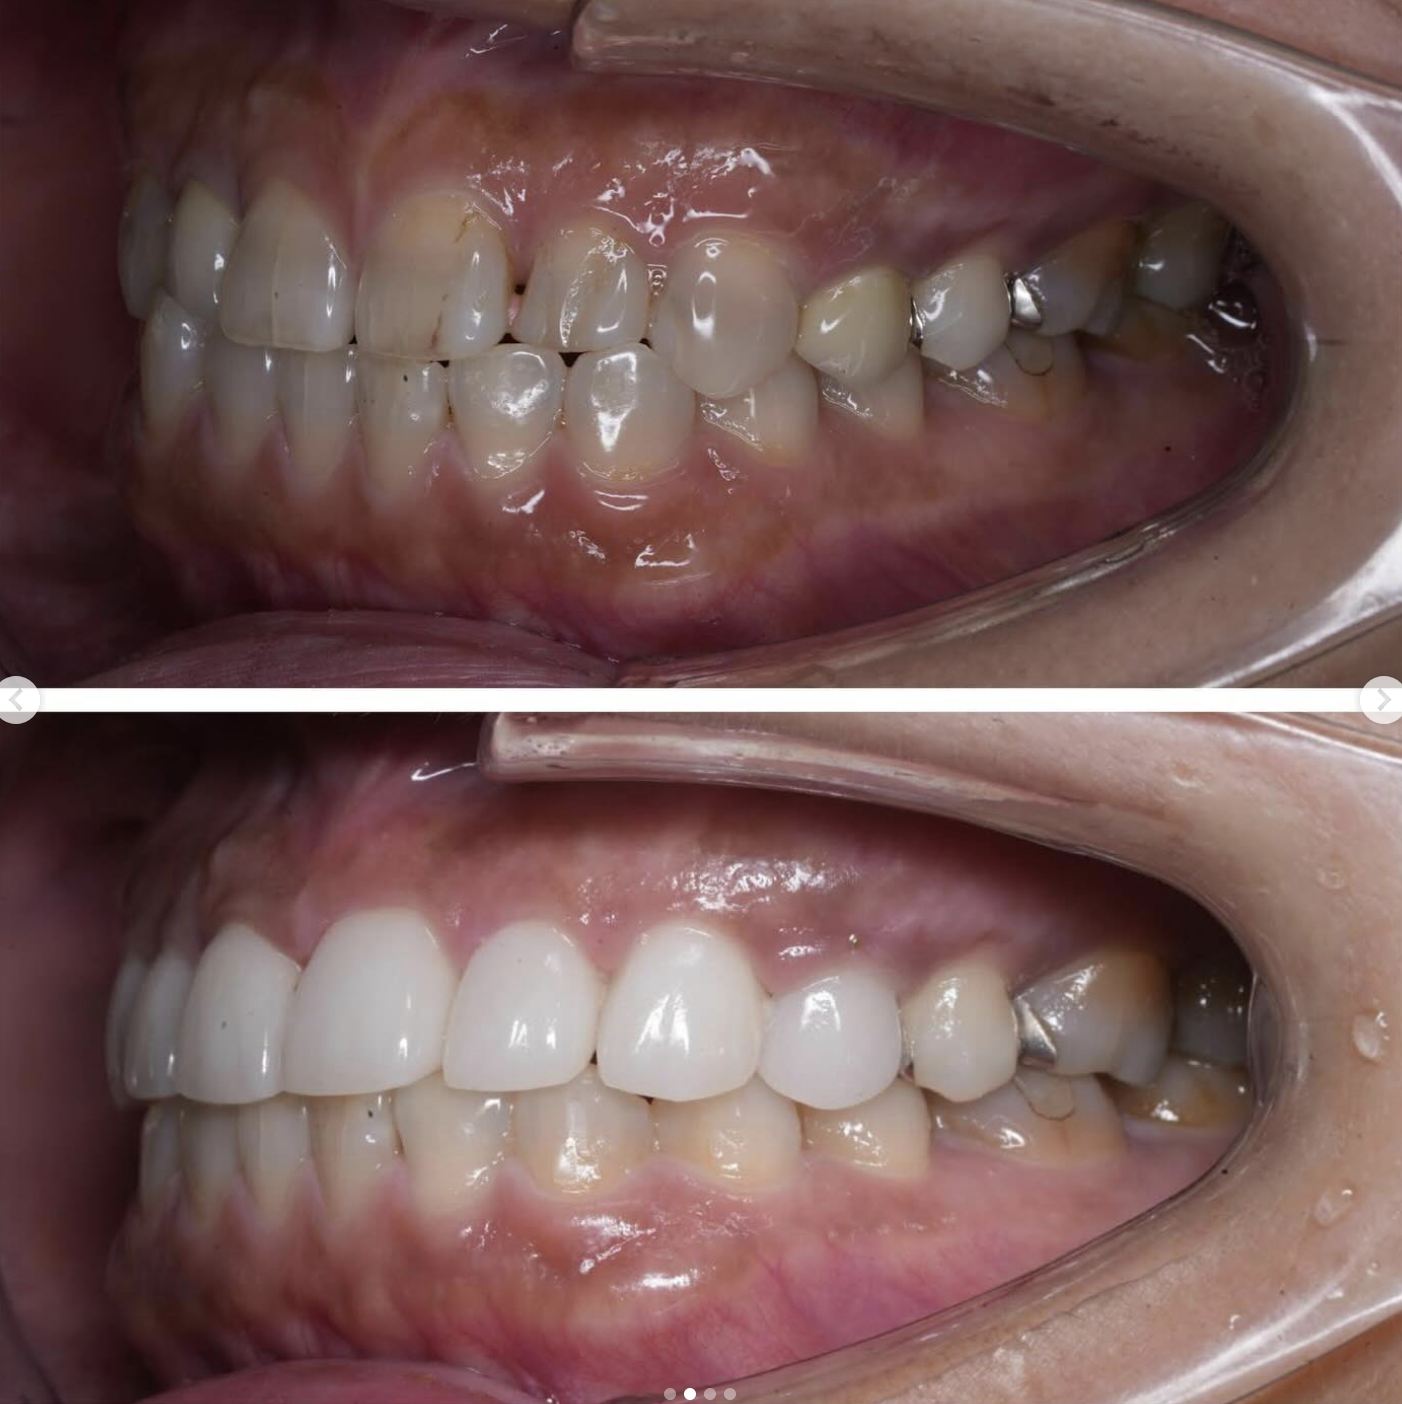

「ずっと放置してしまっていた。今回はちゃんとしっかり治したい」ということで、強い意志をもって来院してくださった患者様の症例です。

インプラント治療、セラミック治療、歯周病治療により、審美性と機能、咬みあわせの再建を行いました。

患者様は咬みあわせの確立により、食事もしやすく、普段の顎関節の状況も良くなり、機能の回復にも満足してくださり、また審美性も喜んでくださいました。

放置期間が長くだいぶ骨が溶けてしまっていたので、前歯部のインプラントは骨の再生療法などが必要だったりしましたが、患者様が治療への前向きな姿勢をだしてくださっていましたので期間も最短で終わりました。